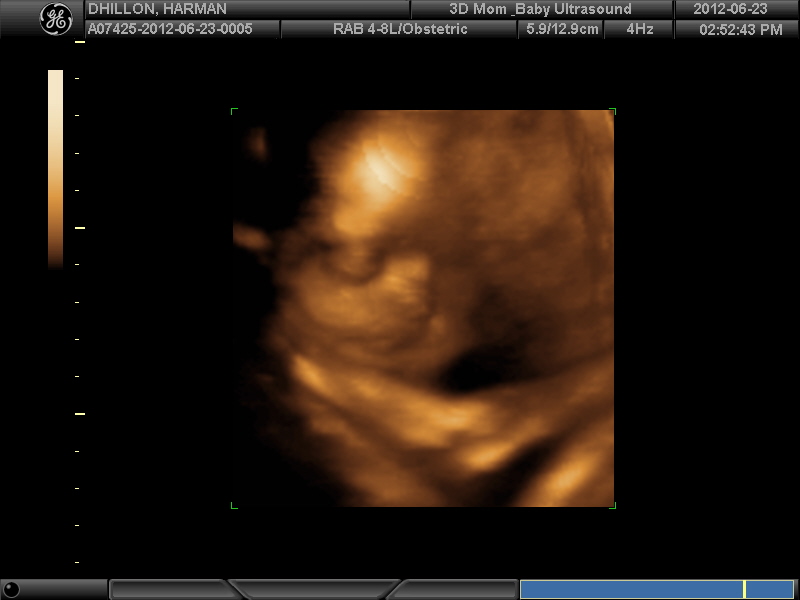

I had a 3D scan yesterday - would love some guesses if possible. Placenta was anterior and hard to find a good position.

I think 3D/4D images arenīt good for gender guessing, beautiful picture of your babies face anyway.